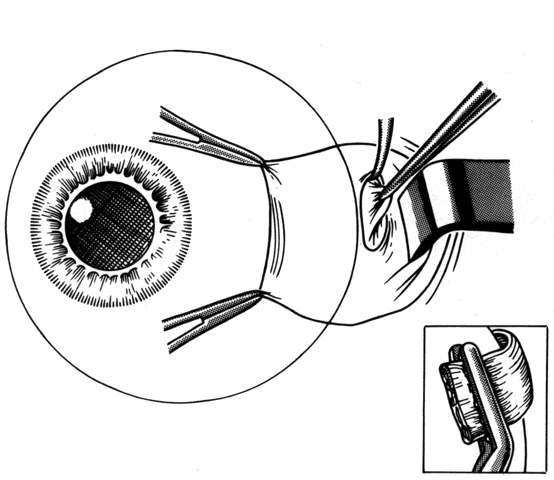

Once the muscle has been cleaned of surrounding adherent tissues, a synthetic absorbable suture is placed into the tendon and secured with lock knots at each pole. The entire muscle must be incorporated in the suture. Bands extending superior or inferior from the insertion (or medial or lateral in the case of vertical rectus muscles) should be cut so that when the muscle has been cut free from the globe, the globe is free to move without restriction. Frequently there will be residual bands of fibrous tissue located on the surface of the sclera. If the globe is pulled in a direction opposite the pull of the bands, these bands will indent the scleral surface, which will facilitate their identification. The passage of a Stevens hook across the sclera will frequently catch on the restrictive bands. Once identified, they can be cut with scissors. After this, the globe will be free to move without restriction.

If a rectus muscle has been recessed 5 mm or more, further recession will put the new insertion at or beyond the arc of contact of the rectus muscle and the globe. This may cause decreased function of the muscle and produce noncomitant ocular rotations, especially in extreme gaze positions. To weaken a rectus muscle without disturbing its insertion site, a marginal myotomy can be performed.39,40 Usually, two separate cuts are made into the muscle near the tendon (Fig. 36) until the muscle lengthens. The weakening effect can be graded by increasing the number of cuts from two to three or by increasing the percent of the muscle that is cut. To be effective, a marginal myotomy should be accompanied by resection of the ipsilateral antagonist muscle.

Fig. 36. To perform a marginal myotomy, the muscle tendon is gently stretched between two Jameson muscle hooks. Prophylactic hemostasis is achieved by clamping the muscle or by application of a wet-field cautery to blanch the vessels in the tendon. The muscle is cut with small “snips” using a Wescott scissors.